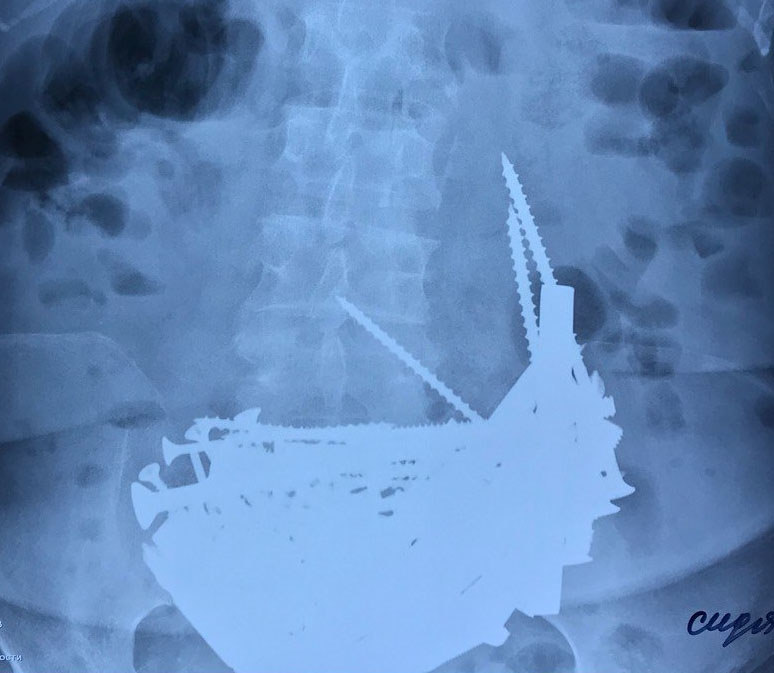

«В желудке находилось огромное количество инородных тел. – сообщает сайт больницы. — При детальном осмотре были обнаружены гвозди, шурупы, болты. Врач попыталась удалить с помощью эндоскопа инородные тела, получилось вытащить 4 гвоздя».

Сделав разрез, врачи добрались до желудка и были шокированы, увидев там длинные гвозди, крупные шурупы, болты, гайки, дверные шпингалеты, отрезки арматуры длиной до 15 см и даже серебряную цепочку 925 пробы. В итоге из желудка пенсионерки было извлечено 152 железных предмета, которые уже начали окисляться. Сколько они там находились, так и осталось никому не известным, кроме самой женщины.

Удалив все 150 с лишним предмета, врачи убедились в том, что стенки желудка у пенсионерки в полном порядке, и нет никакой угрозы для здоровья пациентки. Желудок и брюшную стенку зашили двойным рядом швов.